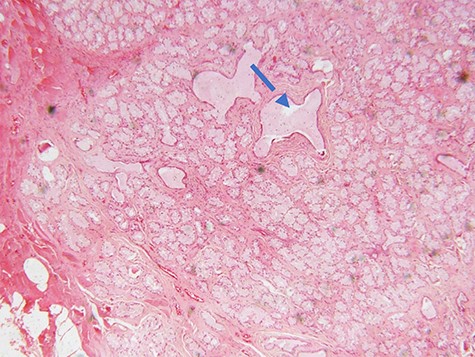

Microscopic examination of the excisional biopsy materials showed a lesion composed of proliferating acinar (Fig. 1) with lining epithelium composed of columnar to cuboidal mucin-secreting cells showing no atypia (Fig. 2). The lesion was divided by fibrous septae to form lobules (Fig. 3). There was a focal area that was showing element of moderate dysplastic changes with element of obliterating tubules, increased hyperchromasia and moderate pleomorphism (Fig. 4). The ratio of duct-to-acini was maintained. Sparse chronic inflammatory infiltrate composed of mainly lymphocytes was present. Neither mitoses nor necrosis were present. The surgical margins were free of the lesion. This confirmed the histopathological diagnosis of Bartholin’s gland hyperplasia with dysplastic changes. After a period of 1 month she was called for clinical evaluation. Healing of the surgical scar was complete and she reported no discomfort or dyspareunia during sexual intercourse.

photomicrograph of haematoxylin and eosin (H and E) stained tissue section showing a lesion divided into lobules by fibrous septae. The typical columnar to cuboidal mucin-producing epithelial cells are basally located with abundant pale cytoplasm (arrow) (×200 magnification)